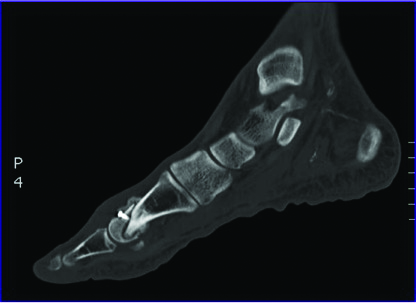

However, one should also utilize imaging modalities to confirm osteomyelitis. While magnetic resonance imaging (MRI) and plain film radiographs are highly sensitive for osteomyelitis, they lack specificity.31 Studies such as Indium-111 and positron emission tomography-fludeoxyglucose-computed tomography (PET-FDG-CT) scans both have a 90 percent sensitivity and specificity in differentiating between marrow edema versus osteomyelitis.31 The clinical suspicion of osteomyelitis warrants the use of bone biopsy as part of the diagnostic armamentarium for determining the presence of active infection. These tools, along with measurement of inflammatory markers and labs, will help distinguish the level of infection and assist in preoperative surgical planning.

We recommend the incorporation of antibiotic-impregnated cement, which is typically non-biodegradable although we have used calcium sulfate antibiotic beads as well. One must be aware that following antibiotic elution, the calcium sulfate beads resorb and form a fibrous granulation tissue rather than a vascular pseudomembrane.